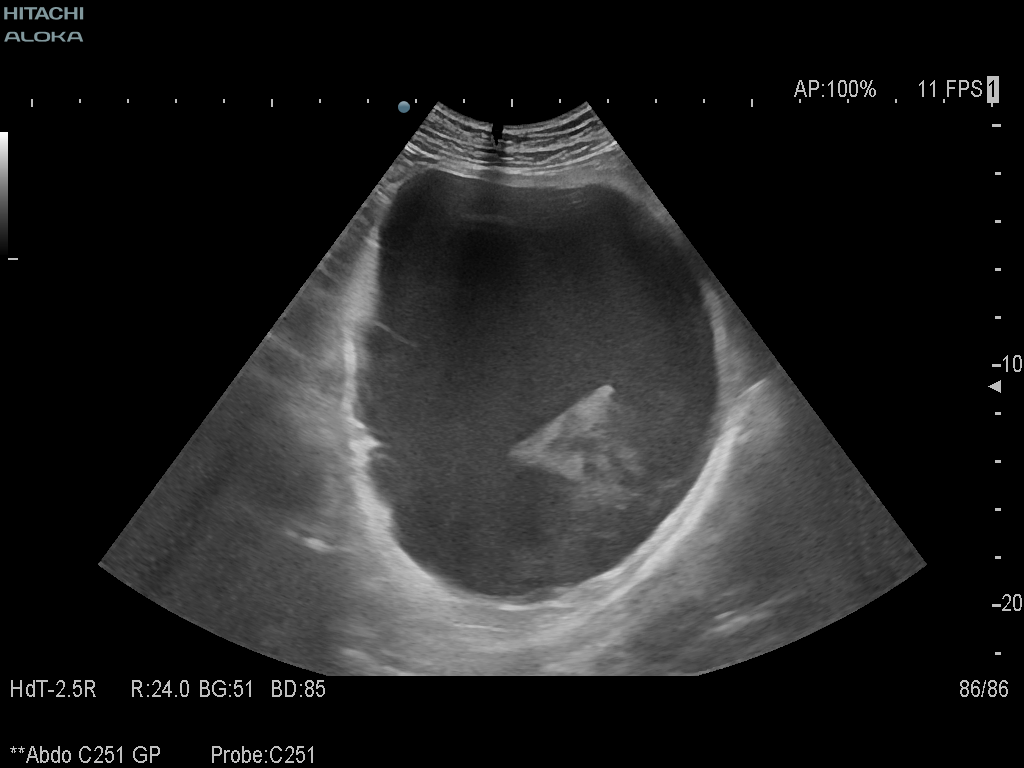

Student Image Challenge 63August 13, 2020Student Image Challenge 65August 26, 2020 Student Image Challenge 64 Student Image Challenge #64 1 / 1 Student Image Challenge #64 A 46-year old male came to the emergency department with extreme physical asthenia and dizziness, with a low hemoglobin count (3.2 mg/dL). Ultrasound examination showed gallbladder stones (up to 2 cm) and a large cyst (17 cm) in the left hypocondrium with hyperechogenic debris inside. What is your diagnosis? Splenic rupture Hemorrhagic adrenal cyst Pancreatic pseudoaneurysm Bleeding pancreatic pseudocyst Adrenal cyst Incorrect ....Please see the correct answer highlighted Correct: Bleeding pancreatic pseudocyst Your score isThe average score is 40% LinkedIn Facebook VKontakte 0% Restart quiz Case courtesy of Prof Adrian Saftoiu EFSUMBAdmin Related postsStudent Image Challenge 107Read more Comments are closed.